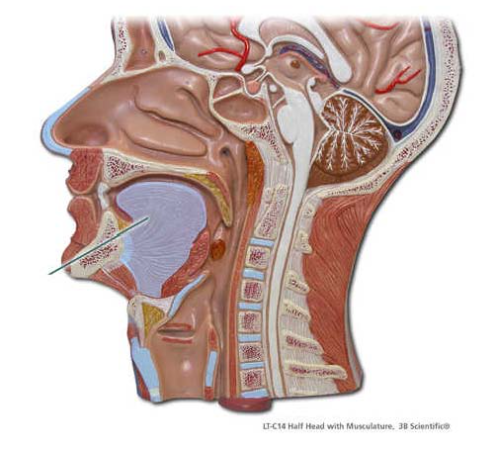

Identify the highlighted structure.

tongue